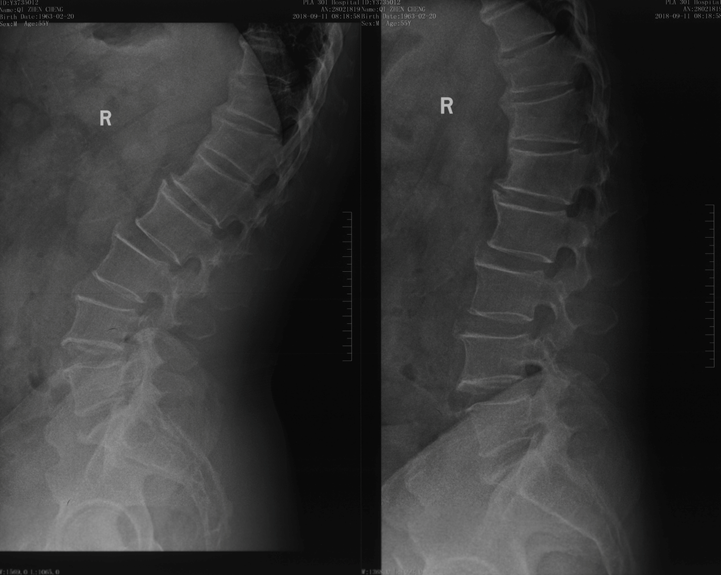

影像资料:

诊断:

>Scheuermann’s病(II型)

TK=53°>45°

TL=42°>30°

T11/T12/L1楔形变>5°

T12/L1许莫氏结节